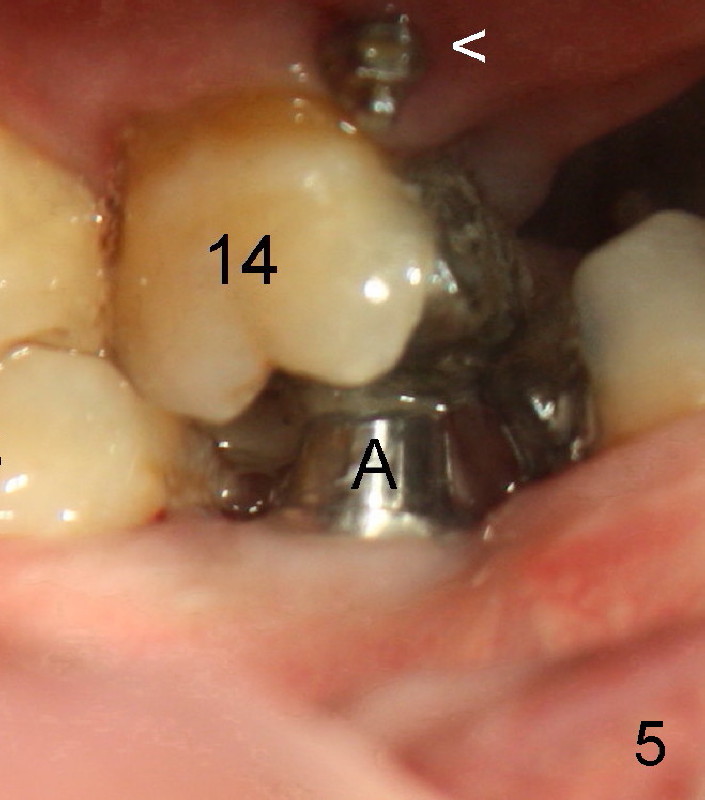

The teeth #15 and 18 cannot occlude when 4.5x5 mm abutment (Fig.4: A) is placed at #19 implant (<). It takes a while to trim the unipost from the top gradually in order to let #15 and 18 have normal occlusal contact (Fig.5 mirror image). By that time, the abutment is approximately 2.5 mm tall.

Arrowhead in Fig.5: mini-implant. In fact two mini-implants are placed (meisobuccal and distolingual) to intrude the supraerupted upper first molar.